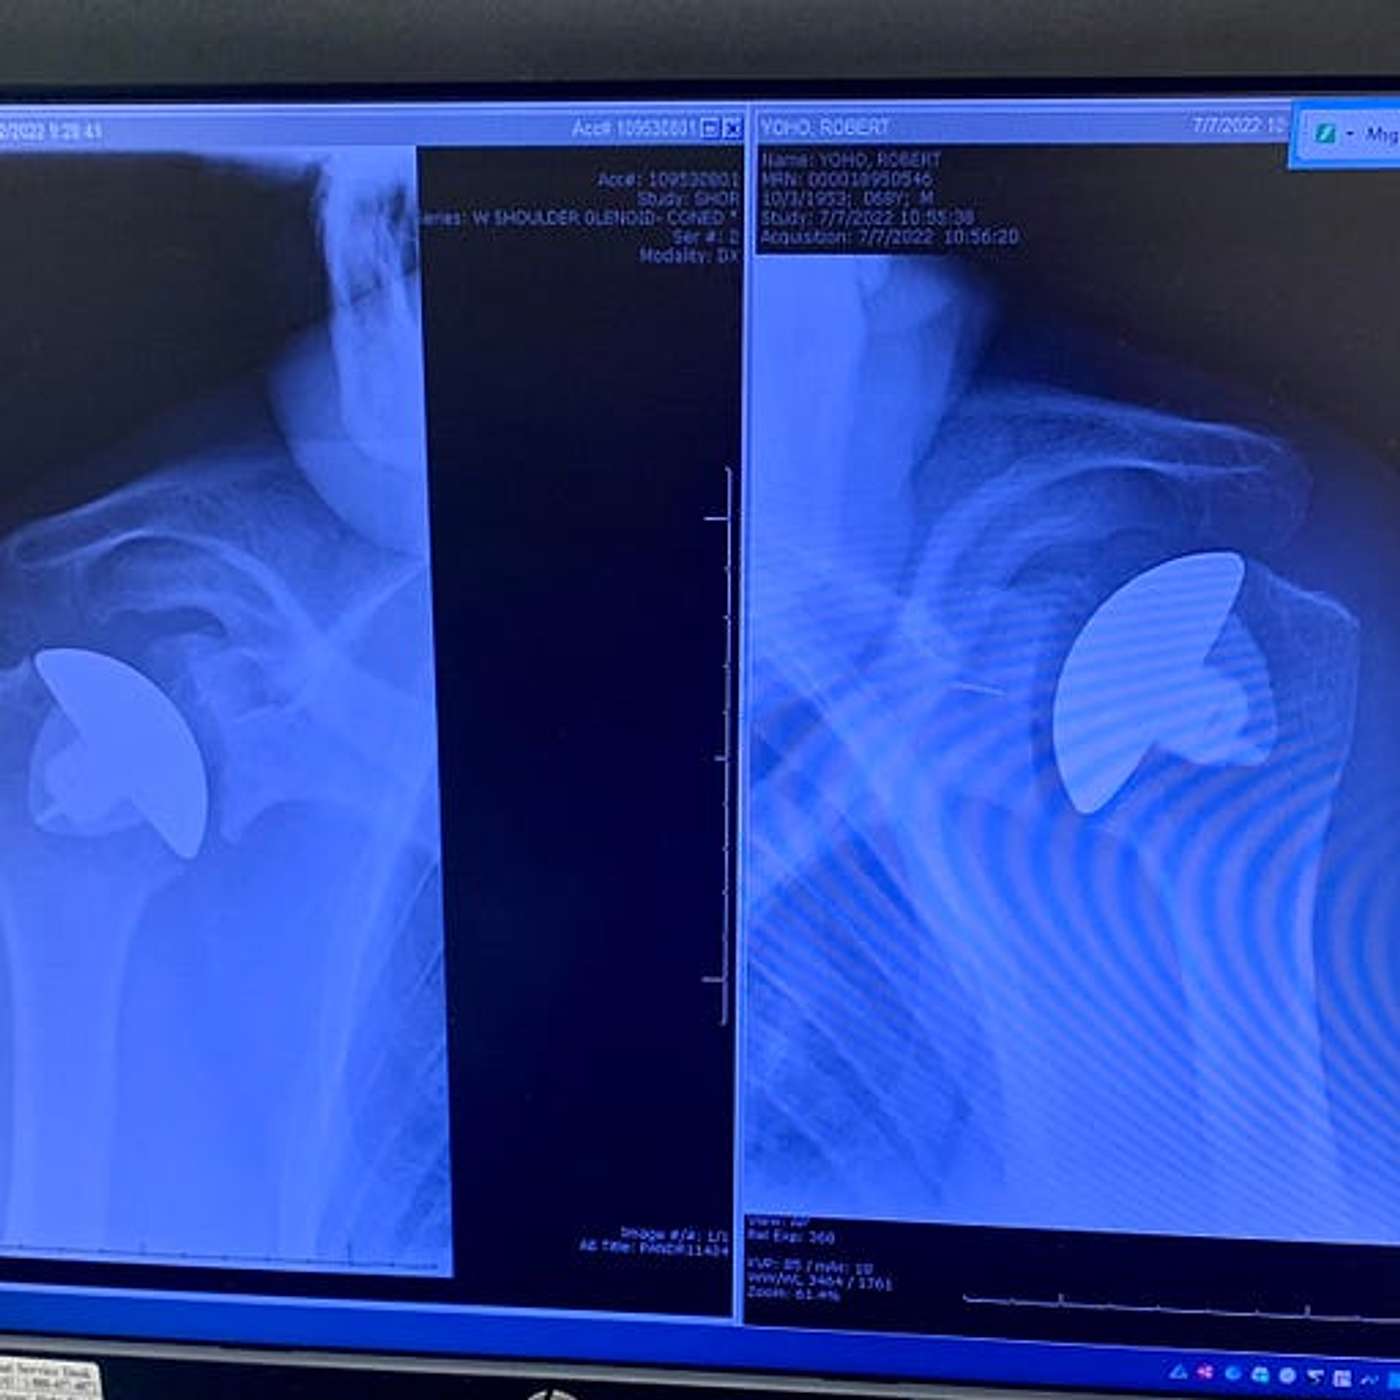

Although knees are done more commonly, shoulder replacements are the second most predictable total joint surgeries after hips. In experienced hands, however, shoulders have excellent results with proper rehabilitation. If your tissues and body are reasonably healthy before the surgery, your chances of a perfect outcome are high. I had little pain and took no opioid painkillers after mine.